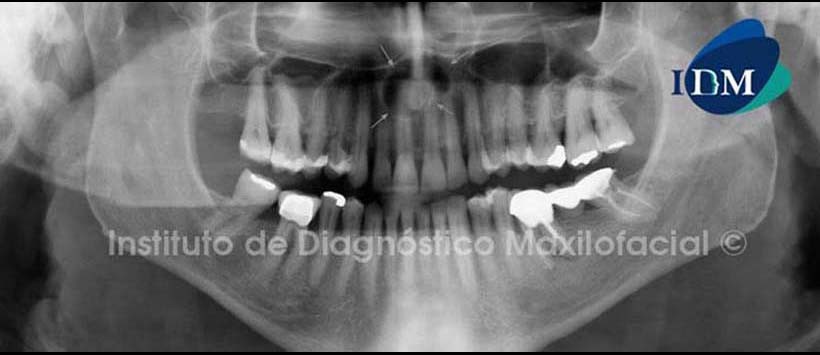

A la evaluación de la radiografía panorámica se observa pieza 36 con corona metal- cerámica, pilar de puente protésico, obturación de conductos y espigo muñón, evidenciándose un proceso osteolítico periapical. Se observa además una imagen radiolúcida de forma redondeada de límites definidos, bordes corticalizados proyectada sobre la línea media maxilar que se extiende desde ápice de pieza 1.2 hasta ápice de pieza 2.2; y desde tercio apical de piezas 1.1, 2.1 hasta proximidades de piso de fosas nasales. (Figura 1)